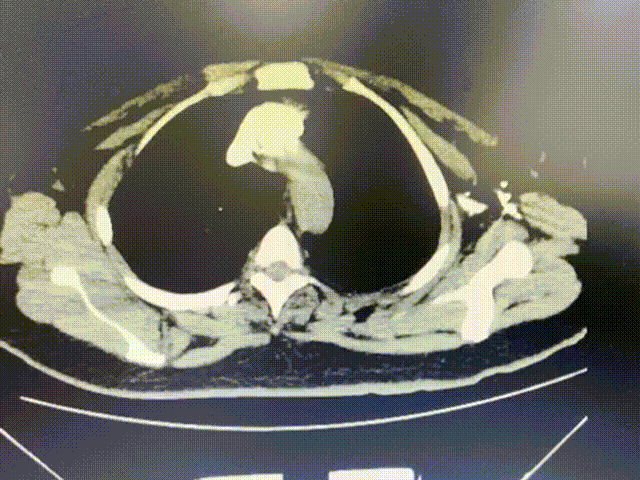

肺动脉CTA未见肺动脉主干有充盈缺损。见下面动态图和静态图。